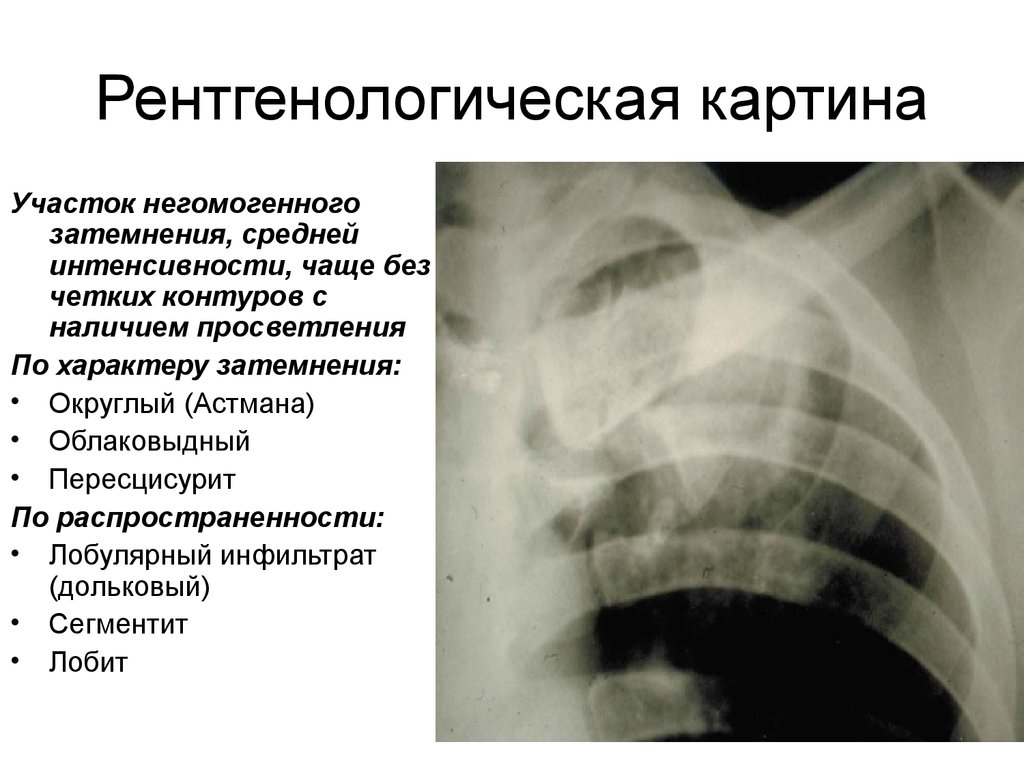

Симптомы и лечение инфильтративного туберкулеза легких

Раздел: Снимки-откровения